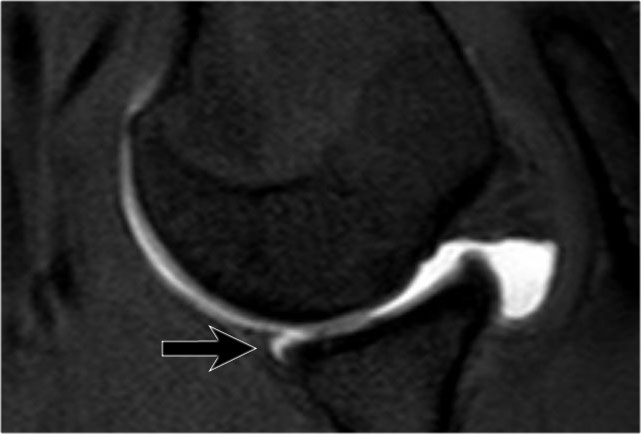

Đây là một bệnh nhân khác có Bankart xương được thấy trên bốn hình ảnh liên tiếp của MRI khớp cản từ ở tư thế ABER.

Lưu ý đường viền bất thường của ổ chảo phía trước và bờ trước bị avulsion (mũi tên)